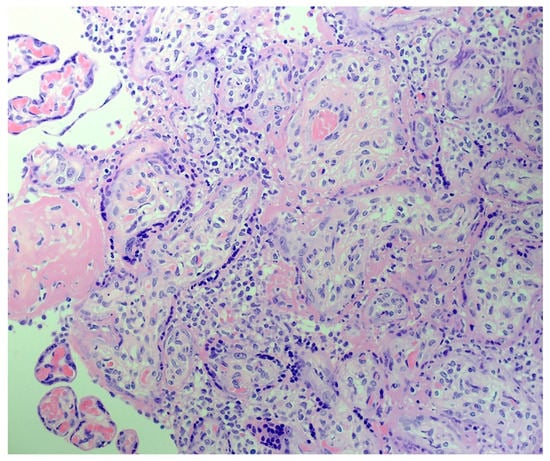

The H&E-stained placental slides demonstrated chronic histiocytic intervillositis, characterized by collections of histiocytes within the intervillous spaces (Figure 1). These histiocytes in the intervillous space stained strongly positive using immunohistochemistry with anti-CD163. In the areas of intervillous histiocytic inflammation, the chorionic villi showed degeneration and necrosis of the syncytiotrophoblast. Immunohistochemical staining with antibody to CD163 also revealed the Hofbauer cells present in the chronic villous stroma (Figure 2). Hofbauer cells appeared as ovoid-to-spindle shaped cells with abundant cytoplasm staining positive for CD163 within varying locations in the chorionic villous stroma. Occasional Hofbauer cells were present in close proximity to the trophoblast basement membrane zone (Figure 2). In some areas, Hofbauer cells were a prominent constituent of the villous stroma, and in some villi, Hofbauer cell hyperplasia appeared to be present (Figure 2 and Figure 3).

Figure 1. Placenta demonstrating chronic histiocytic intervillositis consisting of patchy histiocytic intervillositis with an accumulation of mononuclear inflammatory cells in the intervillous space. H&E. X40.